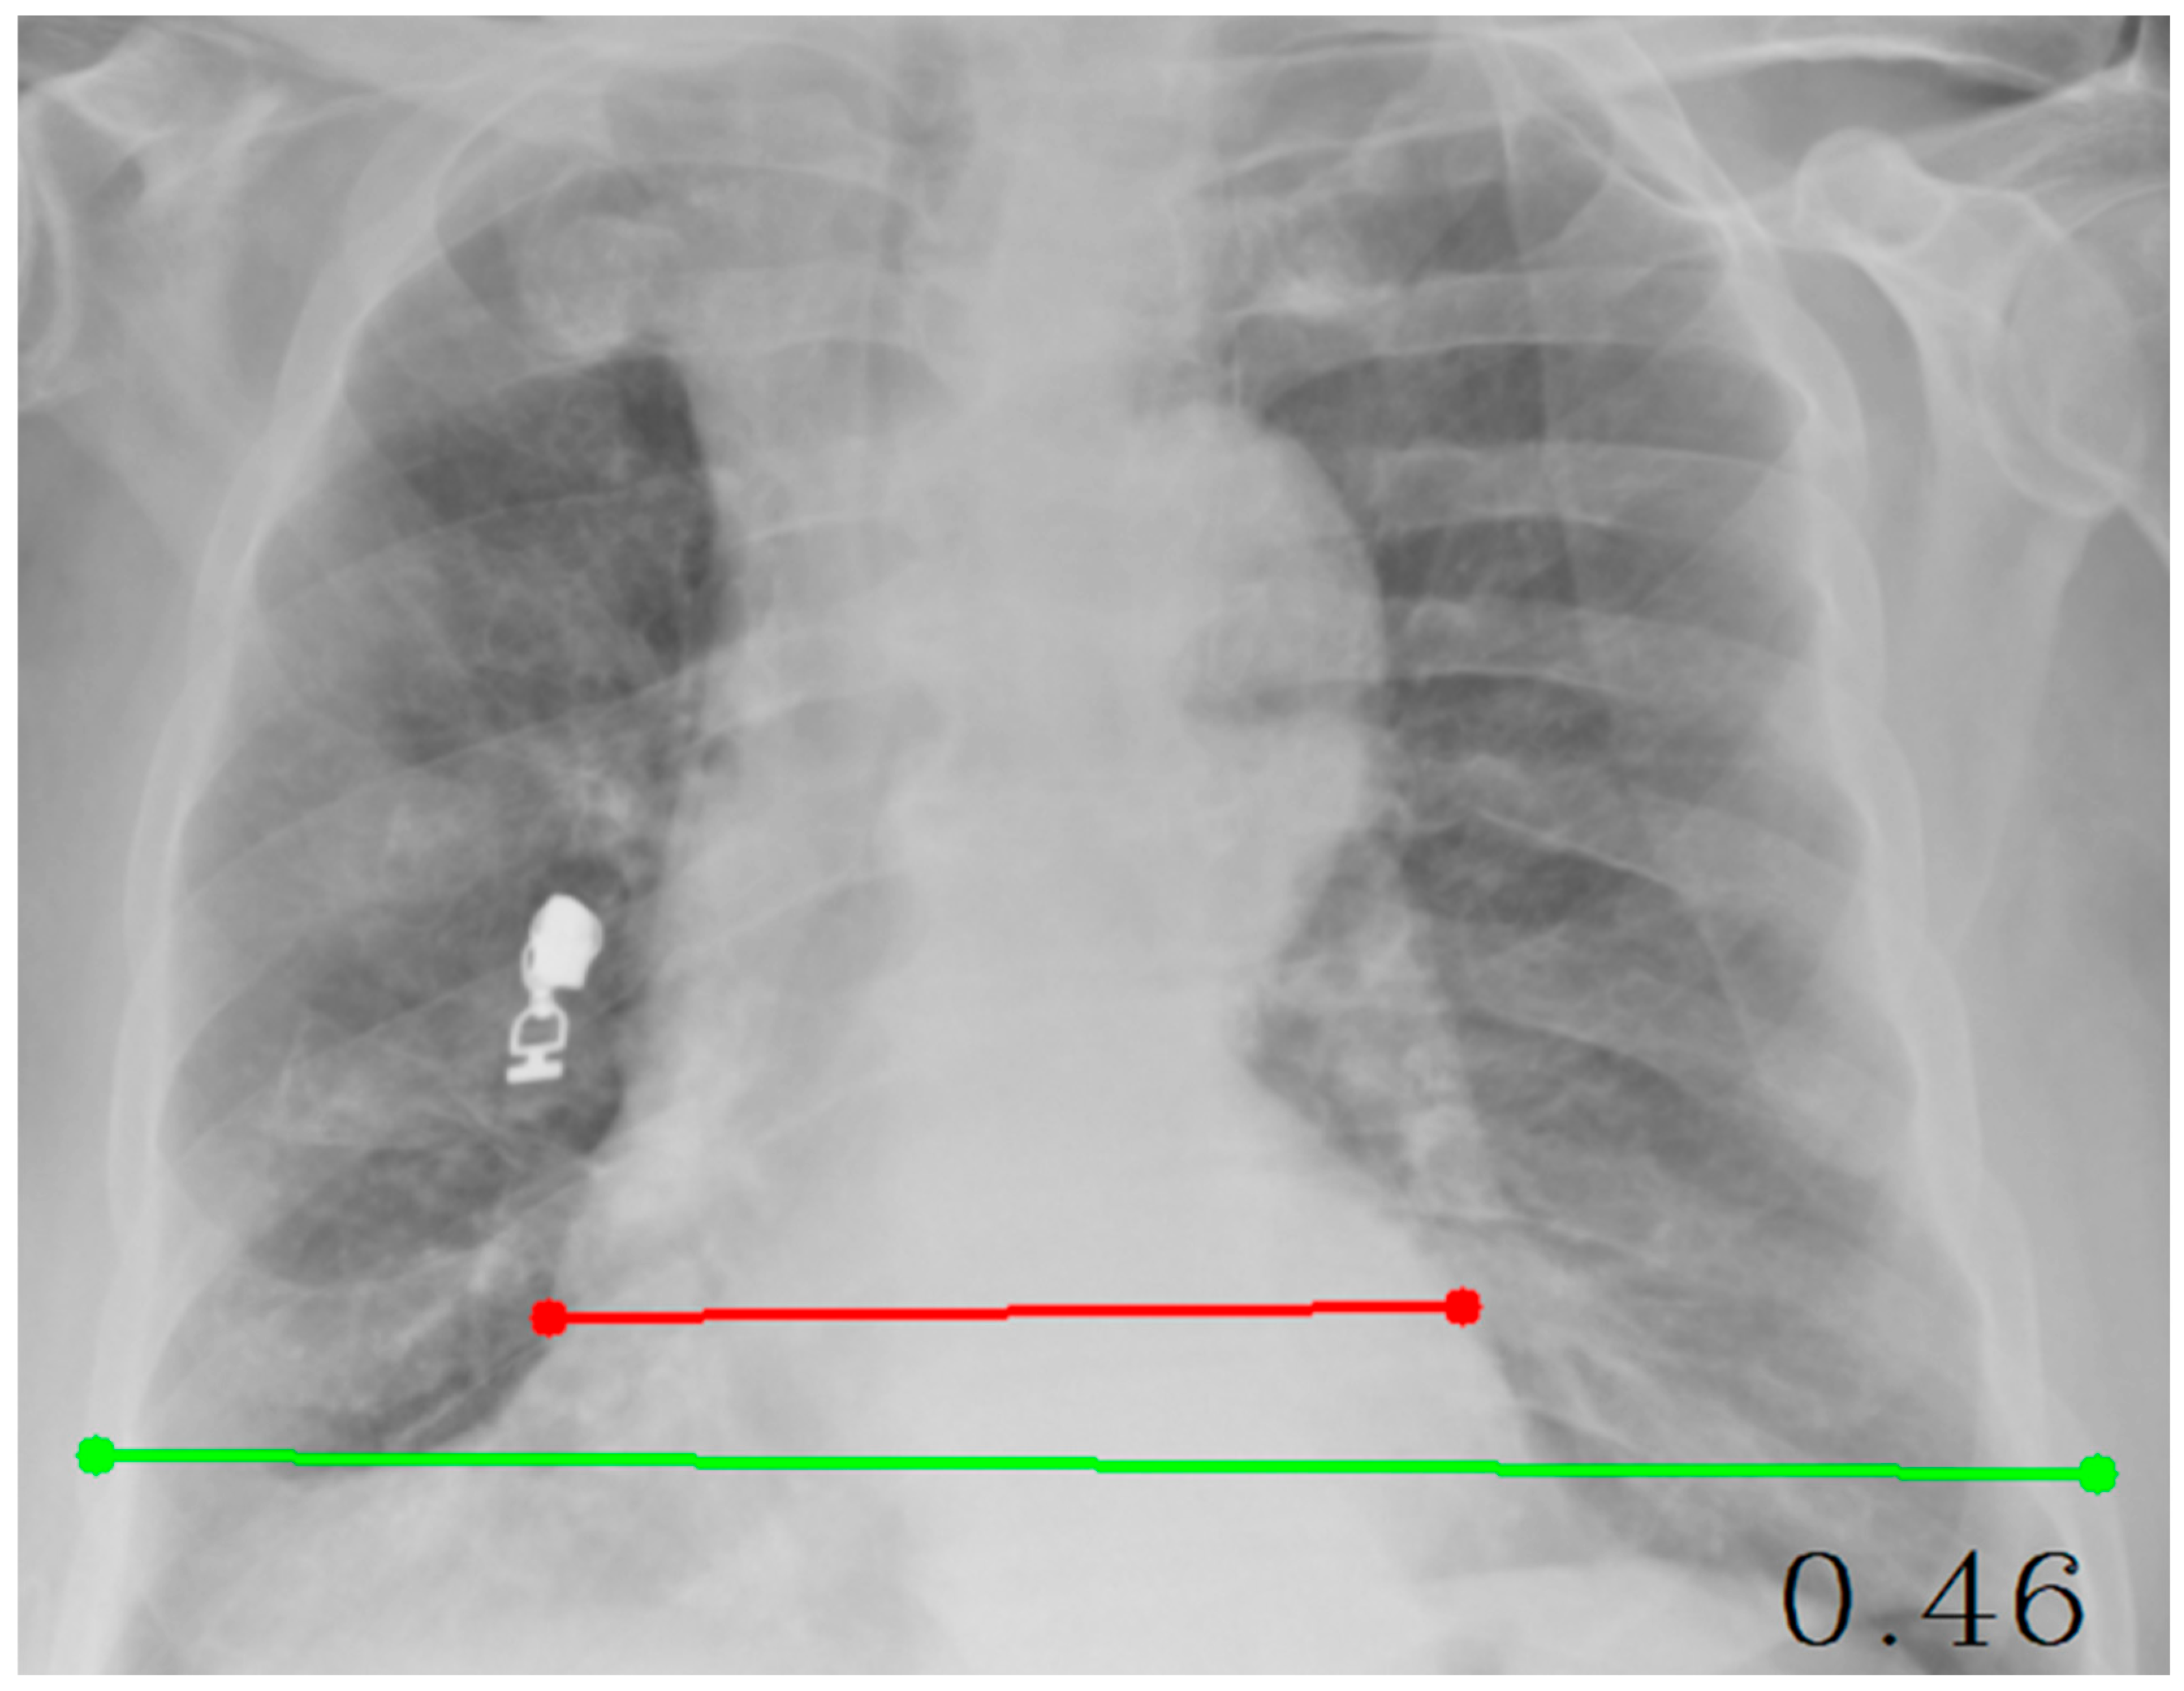

| CTR (Cardiothoracic Ratio) | cv2, numpy, tkinter | Calculates the ratio of cardiac width to thoracic width | Involves point selection and distance measurement |

| Cobb Angle | cv2, numpy, math, tkinter | Measures vertebral tilt and spinal curvature angle | Calculated using four manually selected points |